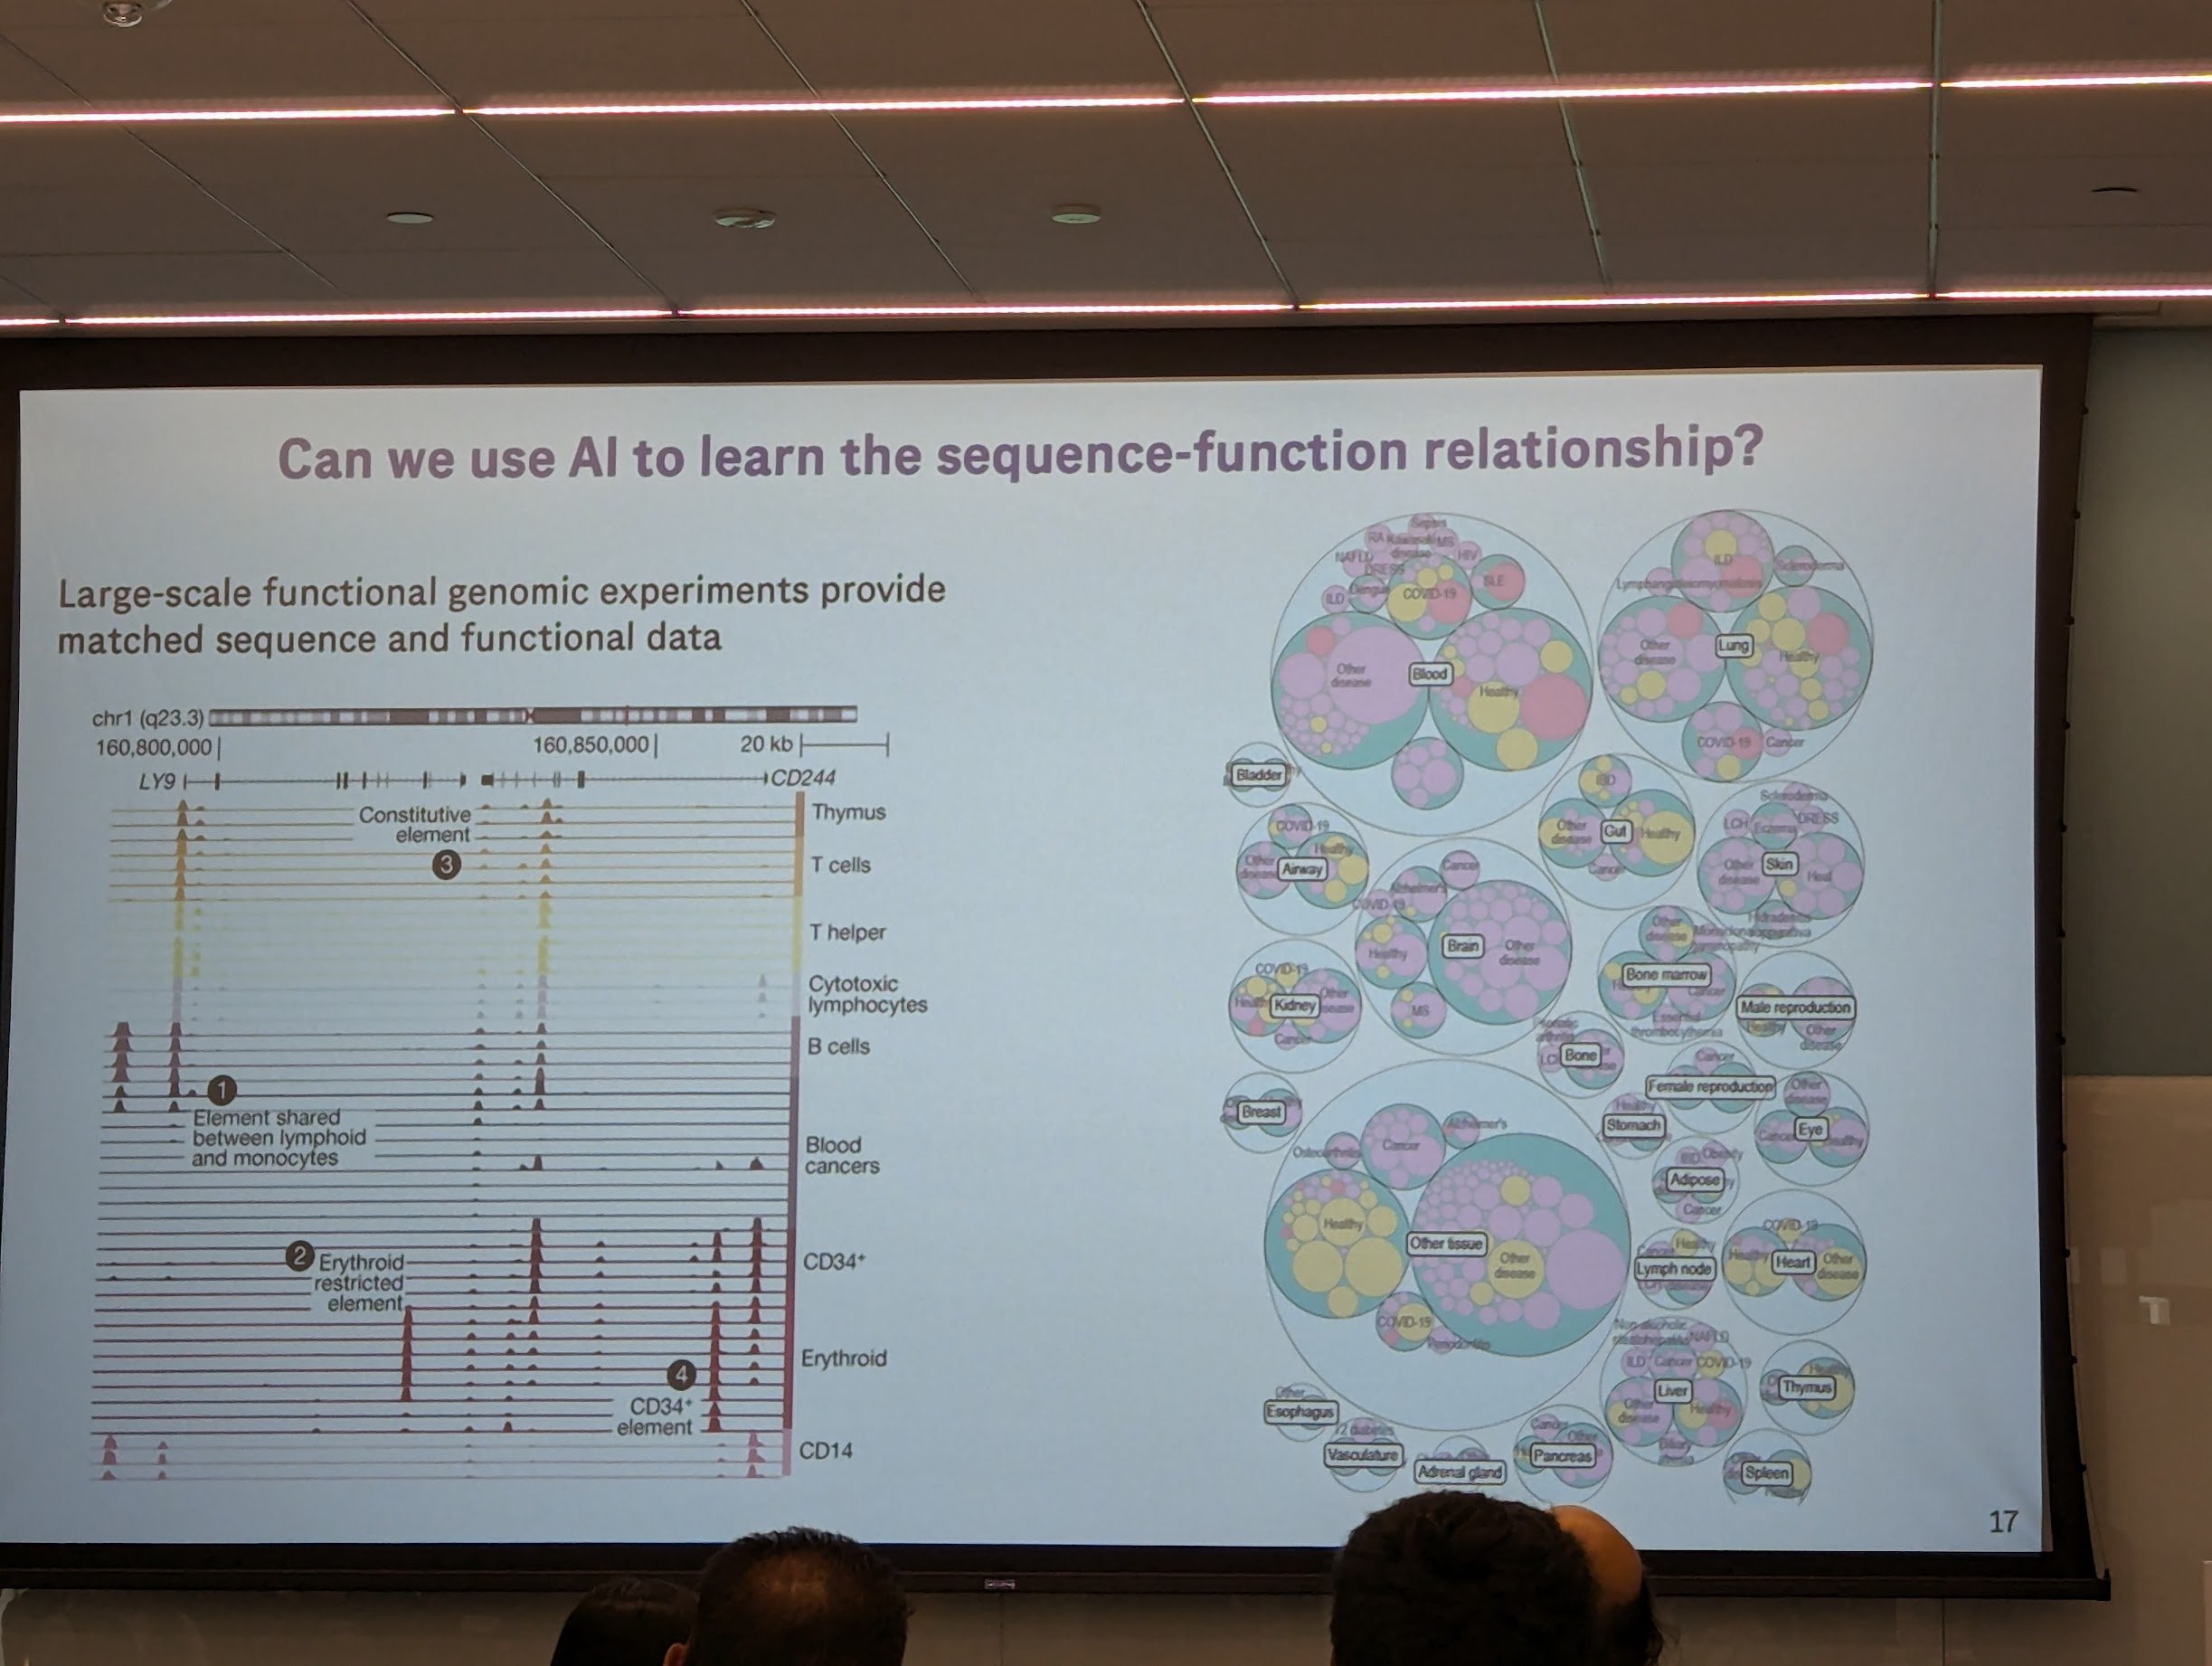

Hosted at Exelixis with a Speaker from Genentech